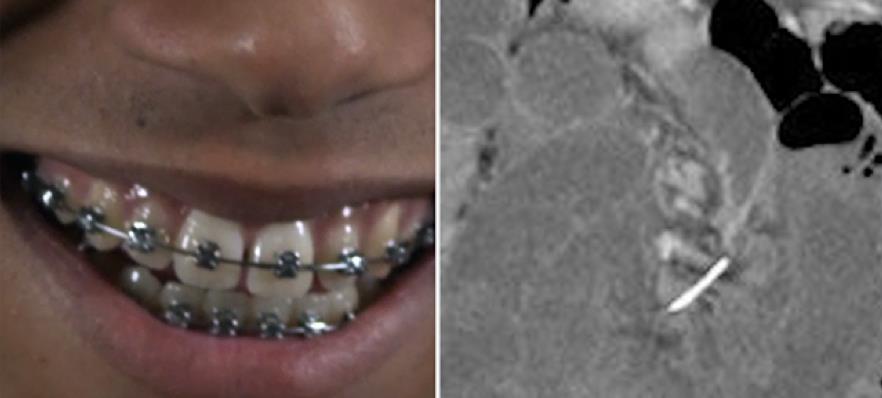

Μια γυναίκα στην Αυστραλία είχε στο έντερό της κομμάτι από σιδεράκια δοντιών για δέκα χρόνια. Η 30χρονη, σύμφωνα με τα όσα μεταδίδει στην ιστοσελίδα του το CNN Health, μετέβη στο Τμήμα Πρώτων Βοηθειών σε νοσοκομείο στη δυτική Αυστραλία με έντονους πόνους στο στομάχι.

Η ασθενής υποβλήθηκε σε ακτινογραφίες και εκεί οι γιατροί διαπίστωσαν ότι στο έντερό της υπήρχε κομμάτι σιδέρου, το οποίο έφραξε μέρος του οργάνου και προκαλούσε το πόνο.

Στην αρχή οι γιατροί νόμισαν ότι επρόκειτο για κομμάτι από κόκκαλο ψαριού, αλλά έπειτα από άλλες εξετάσεις διαπιστώθηκε ότι στο έντερο υπήρχε ένα κομμάτι από τα σιδεράκια της γυναίκας τα οποία η ίδια ανέφερε ότι έβγαλε πριν από δέκα χρόνια. Το σιδεράκι είχε μήκος επτά εκατοστά.